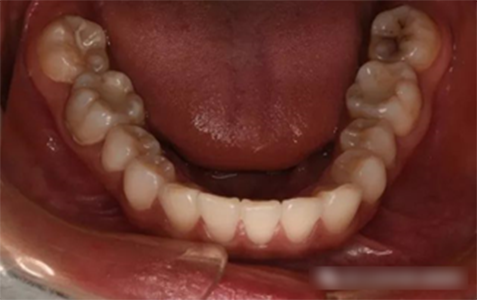

第四、第二恒磨牙較大幾率發(fā)生錯(cuò)合畸形,增加菌斑滯留的機(jī)會(huì)和清潔難度。

2、及時(shí)矯正咬合關(guān)系:第二磨牙錯(cuò)合的概率達(dá)50%以上。應(yīng)及時(shí)選擇合適的方法矯正,形成磨牙區(qū)的正常排列和咬合;